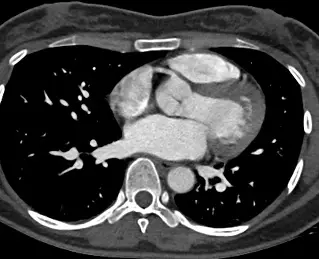

39歲女性,健康檢查時發現有心雜音,進一步做了電腦斷層檢查影像如附圖,最可能的診斷為下列何者?

本題核心在於胸部電腦斷層(CT)影像中,辨識主動脈與肺動脈間的異常交通(ductus arteriosus),與其他主動脈病變(pseudoaneurysm、aneurysm、coarctation)的影像表徵進行鑑別。

– 第三張圖可見心臟與主動脈弓整體解剖無明顯擴張(aneurysm);亦未見主動脈壁局部厚壁破裂或假性囊腔(pseudoaneurysm)的典型血栓層或纖維袋形態。